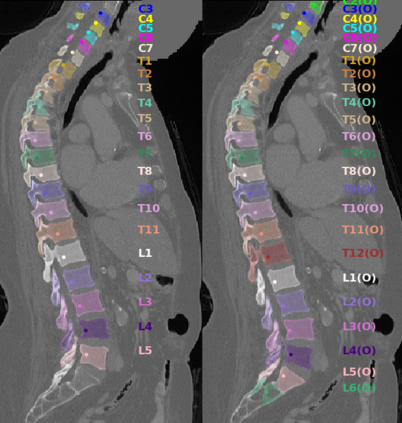

Vertebrae localization, segmentation and identification in CT images is key to numerous clinical applications. While deep learning strategies have brought to this field significant improvements over recent years, transitional and pathological vertebrae are still plaguing most existing approaches as a consequence of their poor representation in training datasets. Alternatively, proposed non-learning based methods take benefit of prior knowledge to handle such particular cases. In this work we propose to combine both strategies. To this purpose we introduce an iterative cycle in which individual vertebrae are recursively localized, segmented and identified using deep-networks, while anatomic consistency is enforced using statistical priors. In this strategy, the transitional vertebrae identification is handled by encoding their configurations in a graphical model that aggregates local deep-network predictions into an anatomically consistent final result. Our approach achieves state-of-the-art results on the VerSe20 challenge benchmark, and outperforms all methods on transitional vertebrae as well as the generalization to the VerSe19 challenge benchmark. Furthermore, our method can detect and report inconsistent spine regions that do not satisfy the anatomic consistency priors. Our code and model are openly available for research purposes.